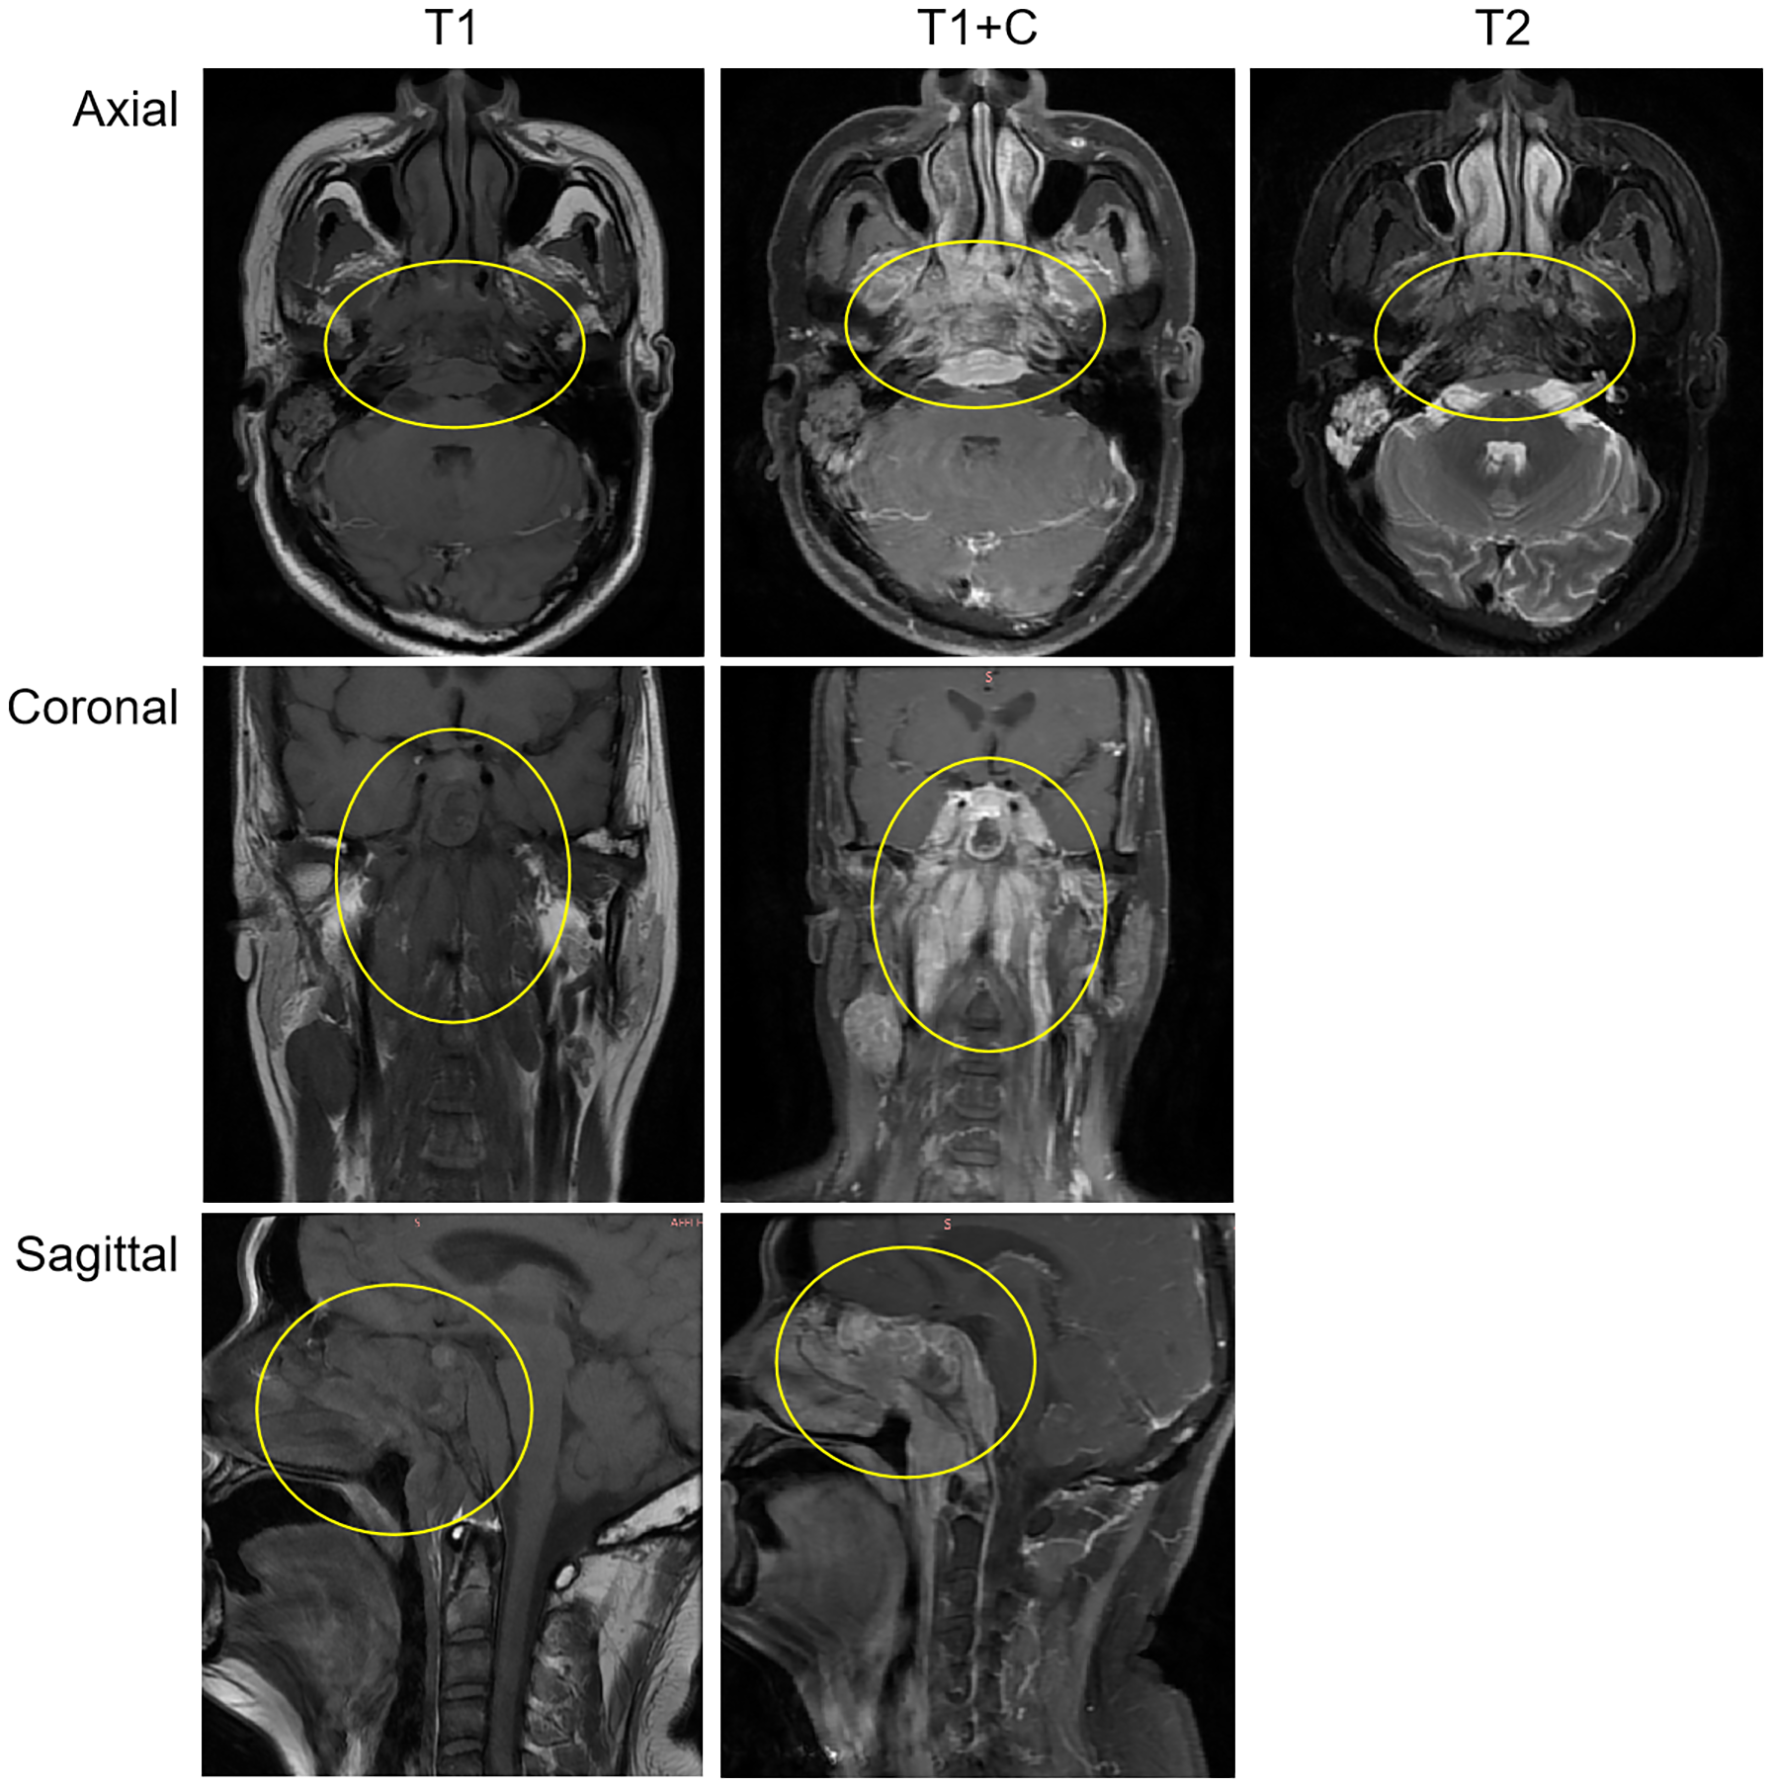

After admission, relevant auxiliary examinations were carried out. Serum tests on March 19, 2024 revealed an elevated cytokeratin 19 fragment (35.600 ng/mL). An EBV-DNA test (whole blood) was performed on March 20 (< 500 copies/mL). Nasopharyngeal and cervical magnetic resonance imaging (MRI) findings from March 20 indicated nasopharyngeal carcinoma with multiple lymph node metastases (Figure 1). The MRI demonstrated mucosal thickening in the nasopharyngeal roof and posterior wall with involvement of the lateral pharyngeal recesses. A soft tissue mass measuring 38 mm×20 mm in the largest axial dimension was identified, which showed isointensity signal on T1 WI and slightly hyperintense signal on T2W with significant enhancement after contrast enhanced scan. Obliteration of the bilateral pharyngeal recesses and eustachian tube orifices was observed. The lesion demonstrated extensive local invasion with encroachment into the parapharyngeal space, pharyngobasilar fascia, etc. Multiple enlarged lymph nodes ranging from small to large were identified in the retropharyngeal space and bilateral cervical levels II; through III and Va, some of which merged into masses. The dominant lymph node, located in the right level III, measured 26 mm×27 mm×35 mm in maximal dimensions. Positron emission tomography-computed tomography (PET-CT) demonstrated a standardized uptake value maximum (SUVmax) of 8.76 in the nasopharyngeal soft tissue mass, with SUVmax values of 7.52 in the bilateral parapharyngeal and cervical lymph nodes and 4.86 in the pulmonary nodule (Supplementary Figure 1).

Figure 1

The MRI demonstrated a soft tissue mass measuring 38 mm×20 mm in the largest axial dimension, which showed isointensity signal on T1 WI and slightly hyperintense signal on T2W with significant enhancement after contrast-enhanced scan. The mass involves the surrounding normal tissue. The findings suggest nasopharyngeal carcinoma; Multiple enlarged lymph nodes, of varying sizes, were observed in the retropharyngeal space and bilateral cervical regions, suggestive of metastatic involvement.